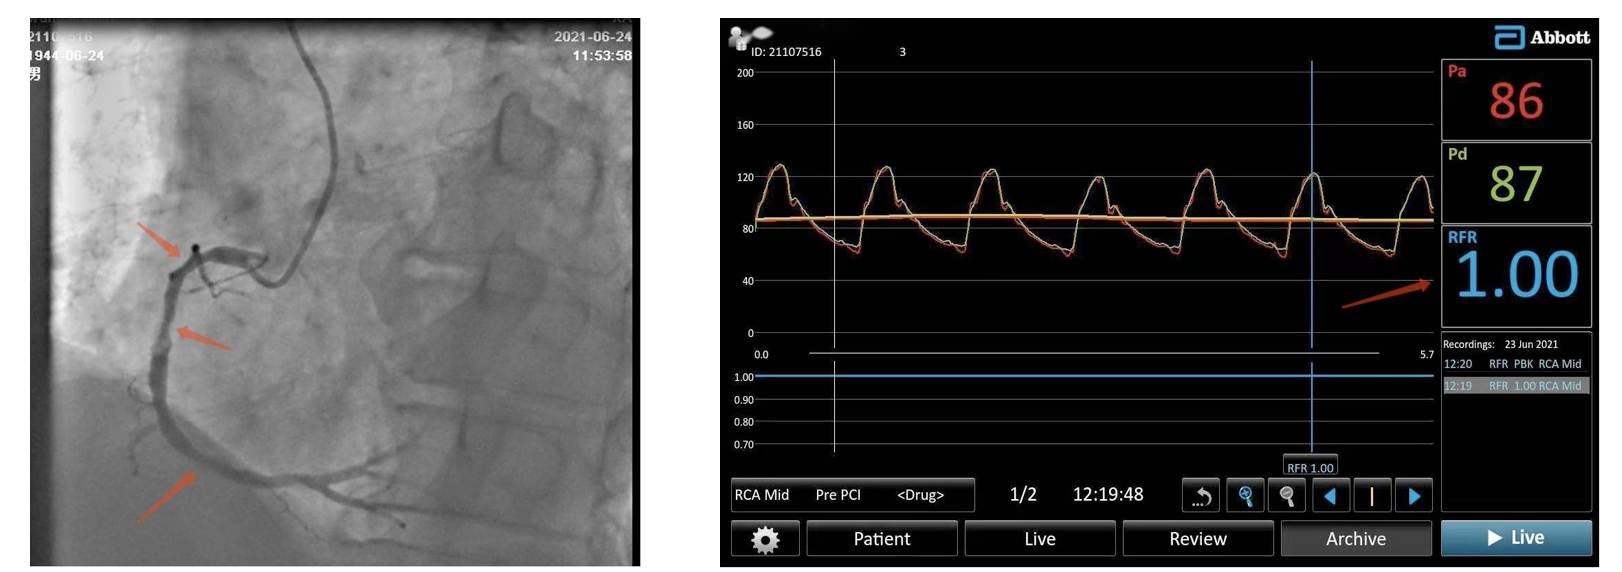

与传统技术相比,RFR指导下介入治疗优势明显,在冠脉压力导丝基础上,不需要注射腺苷,阀值为0.89,灰区为0.86-0.93,准确性及患者舒适性均较好。首例患者为77岁男性,因“阵发性胸痛2年,加重10余天”,门诊以“冠心病,不稳定心绞痛”收入院,既往有高血压、肺气肿及腔隙性脑梗塞病史。冠脉造影显示前降支(LAD)钙化,中段弥漫长病变,最重狭窄85%,D1狭窄50-60%,回旋支(LCX)远段最重狭窄40%,右冠状动脉(RCA)弥漫病变,近段狭窄40%,中段狭窄50-60%,远段狭窄40%。向患者家属讲明病情后,家属同意并于6月24日行RFR指导下介入治疗。

将SAL1.0指引导管置于RCA开口,送压力导丝于RCA远端,测得RFR数值为1.0,即表示为此狭窄没有影响正常的血管功能,明确提示不需要置入支架。